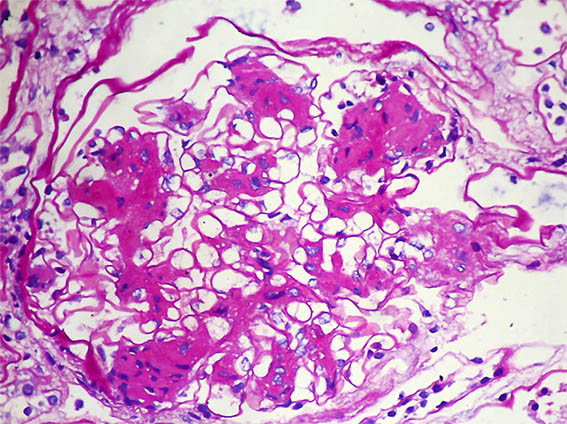

Figure 1. PAS, X400. Mesangial nodules.